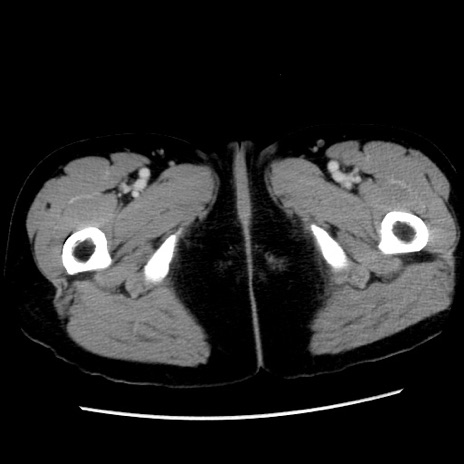

症例10(横断像)

【症例】 50歳代女性

【主訴】 腹痛

【現病歴】前日生レバーを食べた。今朝に排便あり。 昼前に突然発症の腹痛を生じ、当院救急外来を受診した。

【既往歴】 子宮筋腫にてで子宮全摘後

【身体所見】 意識清明、腹部:平坦、軟、下腹部やや左を中心に圧痛・反跳痛あり、筋性防御あり

【データ】WBC 7800、CRP 0.07